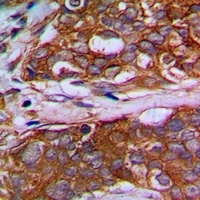

- Experimental details

- Immunohistochemical analysis of MRPL22 staining in human prostate cancer formalin fixed paraffin embedded tissue section. The section was pre-treated using heat mediated antigen retrieval with sodium citrate buffer (pH 6.0). The section was then incubated with the antibody at room temperature and detected with HRP and DAB as chromogen. The section was then counterstained with hematoxylin and mounted with DPX.